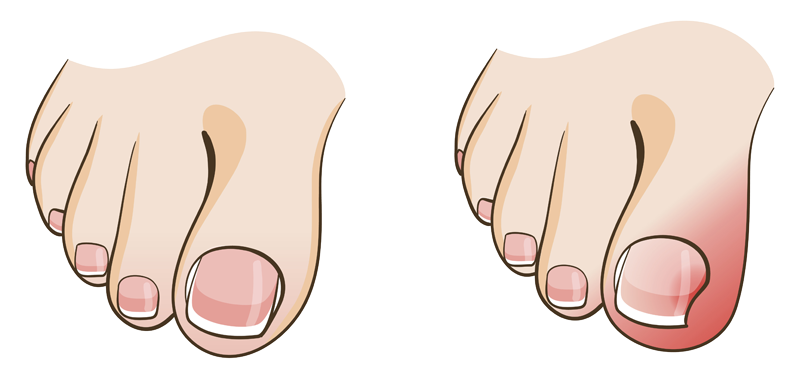

Tırnak Batması Belirtileri

Tırnağın battığı doku etrafında görülen şişlik, kızarıklık ve ağrı şikayetleri, tedavisi geciktirilmemesi gereken bir tırnak batmasının belirtileri olabilir. Hastalığın başlangıç evrelerinde rahatsızlığa sebep olan durumlar ortadan kaldırılırsa ilerlemeden iyileşebilir.